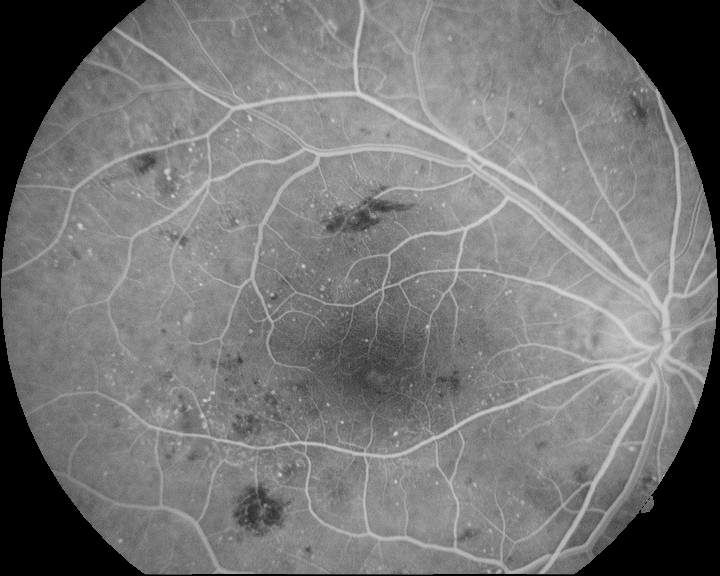

Several experiments are conducted to evaluate the hybrid methodology as well as the performance of the FBR and IBR methods. Regarding the IBR method, both the affine transformation (IBR-AT) and the free form deformation (IBR-FFD) variations are applied. We propose the hybrid method formed by the sequential application of FBR, IBR-AT and IBR-FFD, and alternative variations over this by removing one or two steps at a time. This results in 7 different configurations of methods, as reported in Table 1. The table shows the average and standard deviation VE-NCC for each method in healthy and pathological cases. Figure 3 depicts the cumulative distribution of the VE-NCC values. The best results are achieved by the proposed hybrid method. There is a large difference between the experiments that perform the initial FBR and the ones that directly apply IBR. For the latter experiments the registration failed in most of the cases. Most of the image pairs do not significantly change their VE-NCC values by applying IBR alone, and only a few of them obtained values over the minimum that was achieved by the initial FBR. These results indicate that, with the use of IBR and high order transformations, more accurate registrations can be achieved. However, they also evidence the importance of a proper initialization for the convergence of the optimization algorithm, which is provided by the initial FBR. Moreover, the IBR-FFD also benefits from the previous IBF-AT, as the order of the applied transformation directly fixes the search space dimensionality, increasing the complexity of the optimization. Figure 4 exposes some representative examples of the images registered with the proposed hybrid method. Both the raw images and the vessel enhanced images provide qualitative evidence of a satisfactory multimodal registration with the hybrid approach in healthy and pathological scenarios.

Refer to caption

Figure 4: Examples of the multimodal registration with the hybrid method: (a)(c)(i) retinographies; (b)(f)(j) angiographies; (c)(g)(k) registered image pairs; (d)(h)(l) results of the vessel enhancement operation applied to the registered image pairs.